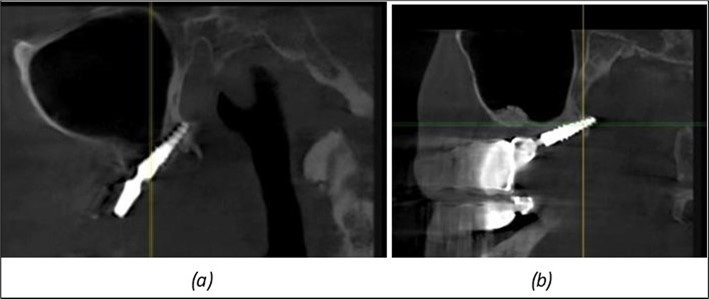

A total of 11 implants is placed in the maxilla, including compressive TPG implants with a polished surface in the maxillary-sphenoid fusion area (Figure 3, Figure 9). Similarly, in the anterior region, final fixation is achieved in the nasal cortex, and BCS corticobasal implants are added in areas with massive bone loss in the frontal region (Figure 3, Figure 8, Figure 11). Additionally, in the palatal sinus cortical area, with the aim of avoiding the addition and sinus lift zone where the second cortical bone no longer exists, 3 implants are placed, 2 in quadrant 1 and 1 in quadrant 2 (Figure 3, Figure 8). Through the Caldwell-Luc sinus lift procedure, the sinus cortical bone is displaced to allow the placement of the graft material and elevation of the sinus membrane. This sinus cortical is no longer recreated at the junction of the graft material and mucosa-sinus membrane, making it impossible to place a corticobasal implant, which relies on the second cortical bone. In the distal mandibular area, after the removal of two stage implants due to massive destruction in quadrant 3, implant placement distal to the mylohyoid line is not possible, as in quadrant 4 (Figure 10). A re-intervention occurs after 5 months to stabilize the area (Figure 12, Figure 14). Also, at the moment of fixation, the tip of one implant fractures, and the decision is made to leave it in place due to regional bone destruction, in order to avoid enlarging the bone defect.

Figure 9.Implants in the pterygoid plateau area: (a) TPG implant fixed in the maxillary-sphenoid junction area, quadrant 1; (b) TPG implant fixed in the maxillary-sphenoid junction area, quadrant 2.

Figure 10.Implants in the palatal sinus cortical area to avoid bone grafting: (a) BCS implant partially fixed in the graft material mass, partially in the palatal cortex; (b) Implant fixed in the palatal cortex at the junction with the nasal cortex, behind the graft material mass.